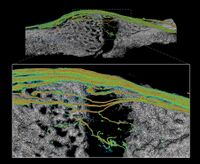

| Research GoalsSkeletal fracture is one of the most prevalent and costly medical issues in the United States, with direct costs exceeding $20 billion annually. In fact, some studies have shown that women over the age of 75 would rather be dead than suffer the consequences of a hip fracture. As a result, the overall goal of the Tomlinson lab is to determine novel mechanisms that augment bone strength and induce the rapid repair of skeletal fractures. In particular, the lab focuses on inflammatory signaling in the skeletal response to mechanical forces and damage using small animal models. The Role of NGF-TrkA Sensory Nerve Signaling in Bone Although sensory nerves are known to be present in mature bone, relatively little is understood about their function in the skeleton, aside from pain. In this project, we are investigating the role of NGF-TrkA signaling in sensory nerves. Nearly all of the nerves in bone express TrkA, the high affinity receptor for nerve growth factor (NGF). Furthermore, sensory nerves blanket the surfaces of bone in a mesh-like network, a privileged location for the acquisition of mechanical signals. Using both in vivo and in vitro methods, we have demonstrated that NGF is robustly expressed by mature osteoblasts in response to non-damaging mechanical loads. Inhibition of NGF-TrkA signaling impairs load-induced bone formation whereas administration of exogenous NGF increases relative bone formation rates. These effects appear to be facilitated through altered Wnt/β-Catenin signaling, which we are currently investigating by using mice which lack NGF in the osteoprogenitor and osteoblast lineages. In addition, we have identified a compound which may provide long-term activation of TrkA to increase load-induced bone formation without the painful side effects of NGF. 1. Tomlinson RE, Li Z, Zhang Q, Goh BC, Li Z, Thorek DL, Rajbhandari L, Brushart TM, Minichiello L, Zhou F, Venkatesan A, Clemens TL. “NGF-TrkA Sensory Nerve Signaling Coordinates Vascularization and Ossification of Bone”, Cell Reports 2016; 16(10):2723-35. PMID: 27568565. PMCID: PMC5014649 2. Tomlinson RE, Li Z, Li Z, Minichiello L, Riddle RC, Venkatesan A, Clemens TL. “NGF-TrkA Signaling in Sensory Nerves is Required for Skeletal Adaptation to Mechanical Loads in Mice”, Proceedings of the National Academy of Sciences 2017; 114(18):E3632-E3641. PMID: 28416686. PMCID: PMC5422802 3. Li Z, Meyers CA, Chang L, Lee S, Li Z, Tomlinson R, Hoke A, Clemens TL, James AW. “Fracture repair requires TrkA signaling by skeletal sensory nerves”, Journal of Clinical Investigation 2019 Dec 2;129(12):5137-5150. PMCID: PMC6877307. 4. Fioravanti G, Hua PQ, Tomlinson RE. “The TrkA agonist gambogic amide augments skeletal adaptation to mechanical loading”, Bone 2021 Jun;147:115908. PMCID: PMC8097708. NSAIDs in Stress Fracture Risk and Repair Non-steroidal anti-inflammatory drugs (NSAIDs) are the most commonly consumed medication in the world, with over 30 million daily users in the United States alone. NSAIDs are effective in reducing pain and inflammation by preventing the synthesis of prostaglandin E2 (PGE2) through the blockade of the cyclooxygenase (COX) enzyme isoforms, COX1 and COX2. However, PGE2 is part of an inflammatory signaling pathway that is known to be critical for load-induced bone formation. In collaboration with our partners at the US Army Research Institute of Environmental Medicine and the Rothman Institute, we have identified a clear link between NSAID usage and stress fracture susceptibility. Furthermore, we have observed in mice that NSAIDs may increase stress fracture risk through two independent mechanisms – diminished load-induced bone formation and decreased bone toughness. In addition, we have identified NSAIDs which can provide analgesia without affecting stress fracture risk or repair. We are currently analyzing the mechanisms by which NSAIDs affect the skeleton, with the aim of uncovering novel therapeutic targets for relieving musculoskeletal pain without affecting bone health. 1. Park J, Fertala A, Tomlinson RE. “Naproxen impairs load-induced bone formation, reduces bone toughness, and diminishes woven bone formation following stress fracture in mice.” Bone 2019; 124:22-32. PMID: 30998998 2. Johnston TE, Dempsey C, Gilman F, Tomlinson R, Jacketti A, Close J. “Physiological Factors of Female Runners With and Without Stress Fracture Histories: A Pilot Study.” Sports Health 2020;12(4):334-340. PMID: 32525466 3. Staab JS, Kolb AL, Tomlinson RE, Pajevic PD, Matheny RW, Hughes JM. “Emerging evidence that adaptive bone formation inhibition by non-steroidal anti-inflammatory drugs increases stress fracture risk”, Experimental Biology and Medicine 2021; Feb 27. PMID: 33641442 NSAIDs in Dental Implant Osseointegration The use of dental implants has transformed the practice of dentistry over the last few decades. The success of this procedure relies on osseointegration, the process by which bone forms a structural and functional connection with the implant over a period of weeks to months. A significant portion of implants fail to osseointegrate, requiring additional surgical intervention. As a result, identifying factors that delay or prevent the osseointegration of dental implants is a top research priority. We hypothesize that use of NSAIDs in the immediate post-operative period may inhibit osseointegration of dental implants. This hypothesis may help explain idiopathic early failure of dental implants, since standard post-operative care often includes immediate and continuous use of high-dose NSAIDs. To directly test our hypothesis, we have assembled a research team of oral surgeons and orthopaedic basic scientists to generate quantitative data from newly placed dental implants as well as analyze bone tissue to ascertain the events that lead to early implant failure. This project is supported by an Osteo Science Foundation grant, in collaboration with our partners in Oral and Maxillofacial Surgery. Bioprinting Vascularized Bone Grafts The main cause of large bone graft failure is poor vascularization which leads to inner graft necrosis. Although this issue has been recognized for some time, developing bone grafts with adequate vascular function has proven to be a difficult problem to address and has prevented the widespread clinical use of engineered bone constructs. In this research area, we utilize 3D bioprinting to generate vascularized bone graft using patient-specific imaging data. First, we are developing a new computational tools to provide semi-automated generation of vascular structures within volume generated from standard clinical imaging. Next, we are optimizing the parameters used for extrusion bioprinting to improve outcomes and reproducibility using a type II fuzzy system. Our ultimate goal is to use bioprinting to generate patient-specific vascularized bone grafts for repair of carpal bones and other small bones with complex geometry and articulating surfaces. 1. Sedigh A, DiPiero D, Shine KM, Tomlinson RE. "Enhancing Precision in Bioprinting Utilizing Fuzzy Systems", Bioprinting. 2022 March. doi: 10.1016/j.bprint.2021.e00190. 2. Morrison DG, Tomlinson RE. “Leveraging advancements in tissue engineering for bioprinting dental tissues”, Bioprinting. 2021 Aug;23. doi: 10.1016/j.bprint.2021.e00153. Epub 2021 Jun 13. PubMed PMID: 34268456; PubMed Central PMCID: PMC8276871. 3. Sedigh A, Akbarzadeh-T MR, Tomlinson RE. "Comparison of Type-1 and Type-2 Fuzzy Systems for Mineralization of Bioprinted Bone", bioRxiv. 2021 March. doi: 10.1101/2021.03.31.437908. 4. Sedigh A, Tulipan JE, Rivlin MR, Tomlinson RE. "Utilizing Q-Learning to Generate 3D Vascular Networks for Bioprinting Bone", bioRxiv. 2020 October. doi: 10.1101/2020.10.08.331611. Other Research AreasCheck out our Publications. |